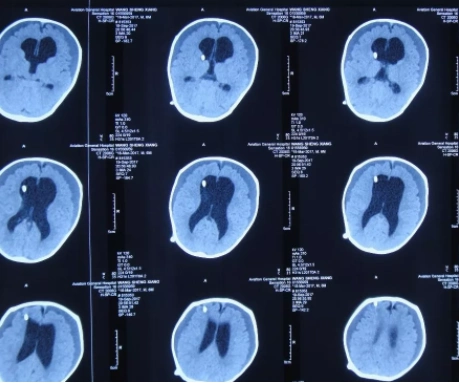

广州医科大学附属第五医院 病例分享:婴幼儿脑积水病例分享

落日征 脑积水

脑积水一例